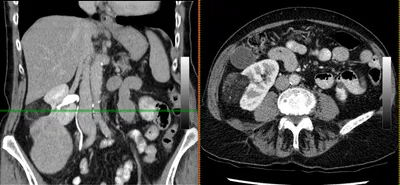

Mesenteric lymphadenitis

CTAbdomenCoronal+1

4/23/2026